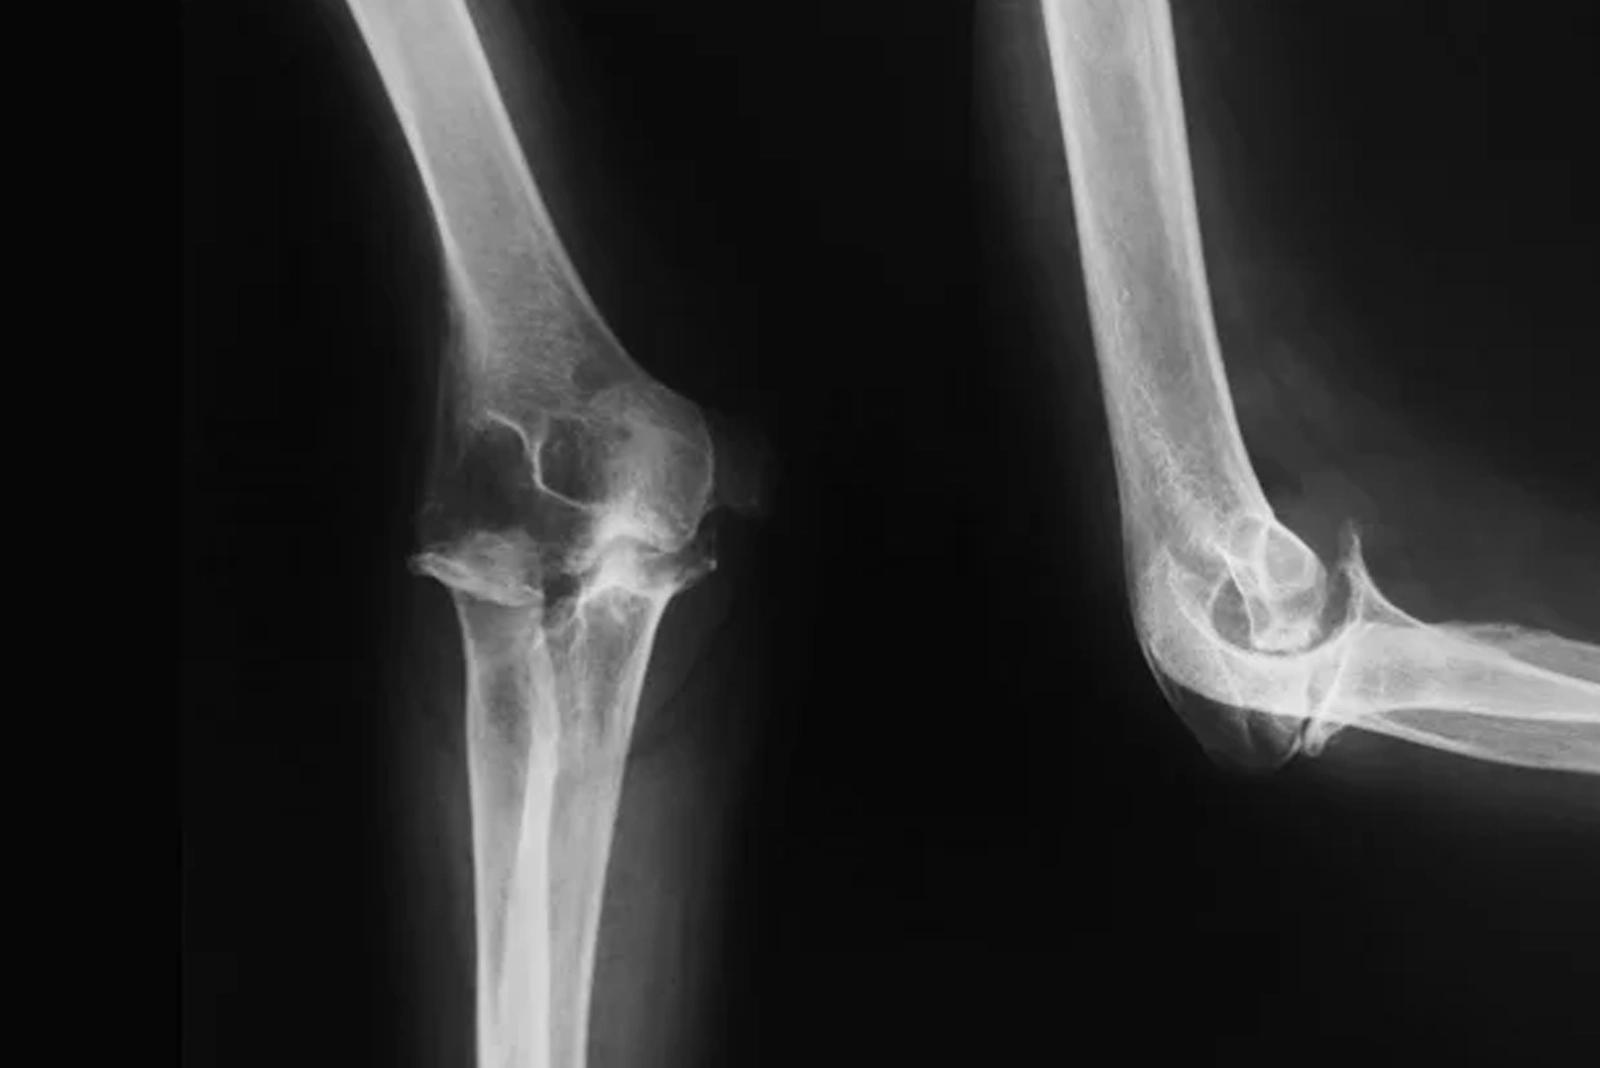

Understanding Elbow Anatomy

The elbow is a complex joint consisting of three bones: the humerus, radius, and ulna. The movements that can be performed by this joint are flexion, extension, and forearm rotation. The joint is encapsulated by muscles, tendons, ligaments, and bursae, which enable it to move smoothly. Pain could be a result of inflammation, degeneration, or trauma to any of the above structures. Understanding the underlying cause is key to effective elbow pain treatment in Bangalore.

Diagnosis of Elbow Pain